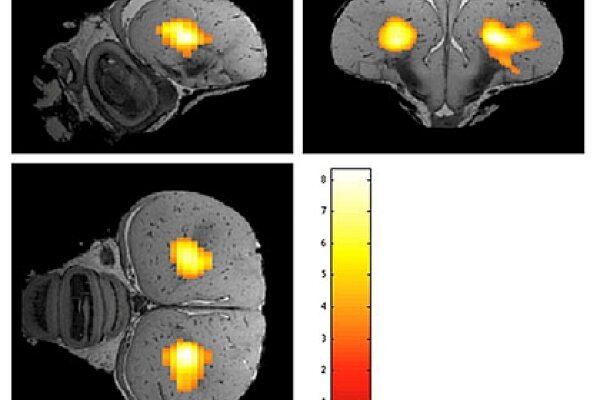

Functional MRI (fMRI) is widespread in humans but still rare in animal research. If being applied, nearly always anaesthetized animals are used. Only a few articles present results obtained in awake rodents. With advent of the "cognitive bird revolution", awake bird fMRI is increasingly relevant. Bioimaging experts from Antwerp and Biopsychologists from Bochum now conducted the first awake bird imaging study with highly habituated and head fixed pigeons. Both traditional fMRI and resting state (rsfMRI) were applied. In addition, this is the first time functional connectivity measurements were performed in a non-mammalian species. Since the visual system of pigeons is a well-known model for brain asymmetry, the focus of the study was on the neural substrate of the visual system. For fMRI a visual stimulus was used and functional connectivity measurements were done with the entopallium as a seed region. Interestingly in awake pigeons the left E was significantly functionally connected to the right E. Moreover connectivity maps for a seed region in both hemispheres resulted in a stronger bilateral connectivity starting from left E. These results could be used as a starting point for further imaging studies in awake birds and also provide a new window into the analysis of hemispheric dominance in the pigeon.

De Groof, G., Jonckers, E., Güntürkün, O., Denolf, P., Auderkerke, J.V., Van der Linden, A. (2013). Functional MRI and functional connectivity of the visual system of awake pigeons. Behavioural Brain Research, 239, 43-50.